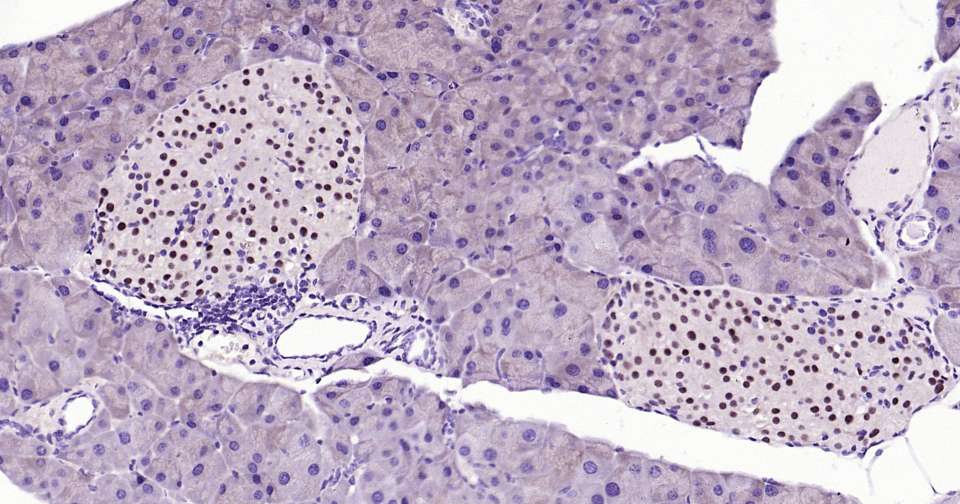

Immunohistochemical analysis of paraffin embedded human pancreas tissue slide using IHC0367 (PAX6 Kit).